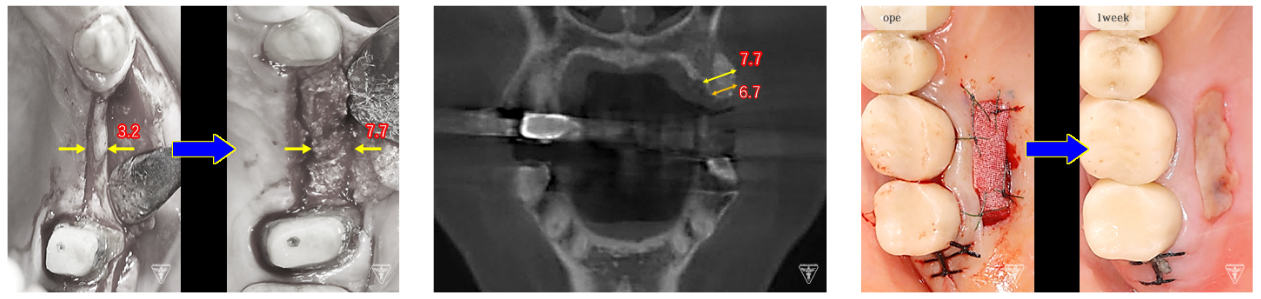

骨再生治療

インプラント